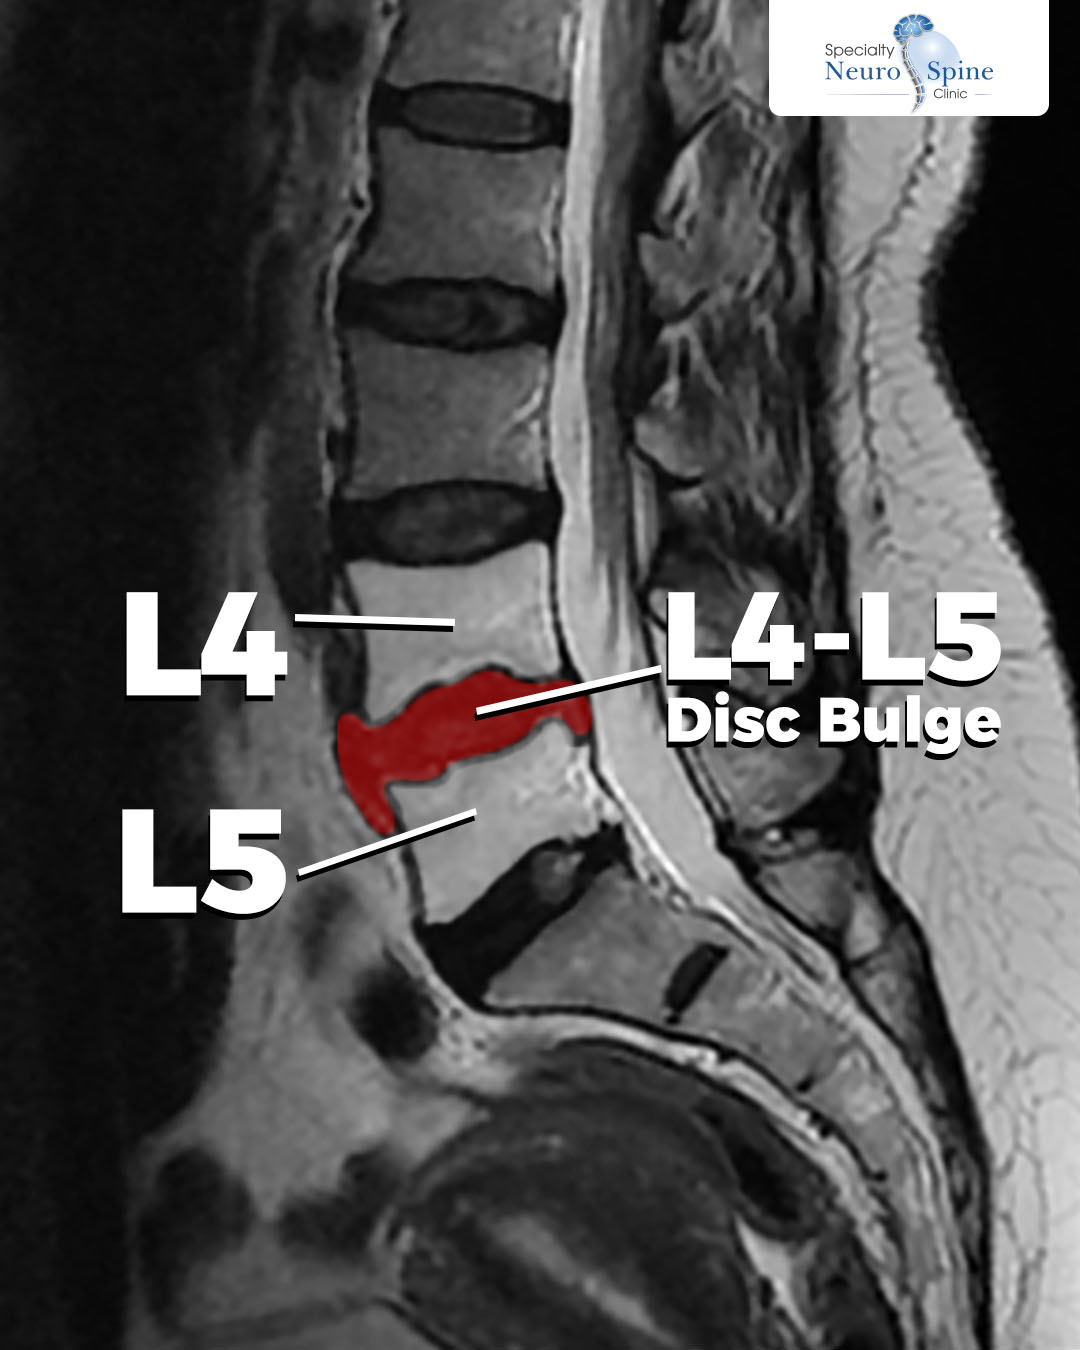

X-ray images of our dear patient, Rasha (49 years old from the West Bank), reveal a herniated disc at the L4-L5 lumbar vertebrae. This was the primary cause of the severe pain, numbness, and walking difficulties she endured.

This diagnostic stage is a fundamental step in precisely tailoring the optimal treatment plan prior to surgical intervention.